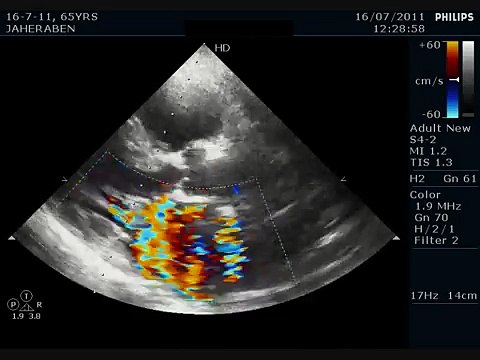

HOCM, WITH, Systolic, anterior, Motion, Mitral, Leaflet